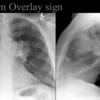

Hilum overlay sign

Mass in front or behind hilum

Date: 04/28/2014

Views: 5223

see next image

Views: 3619

Views: 4525